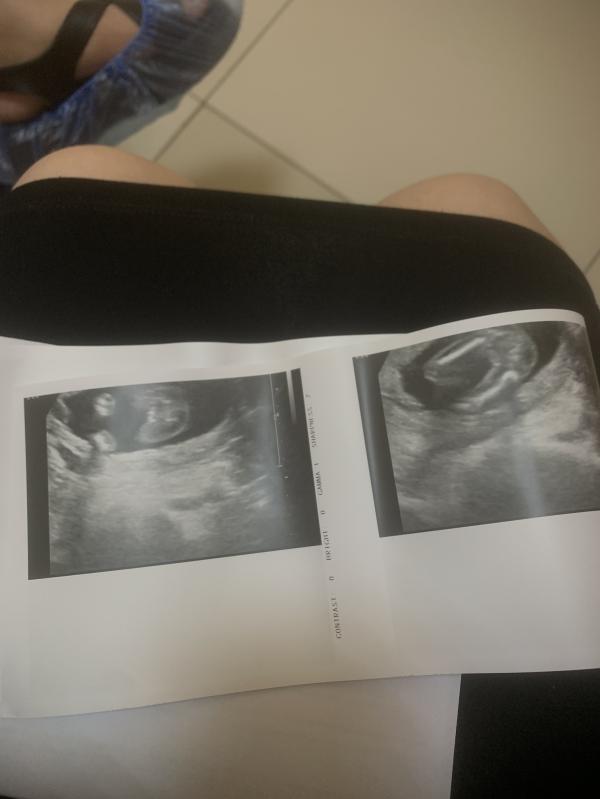

Узнали пол малыша на УЗИ — кто у нас? Смотрим фото!

Ходила на узи, узнали пол . ❤️

Думаю по фотке все понятно , кто у нас 😂

Девочка😍 Поздравляю 🤗

Девочка 💞